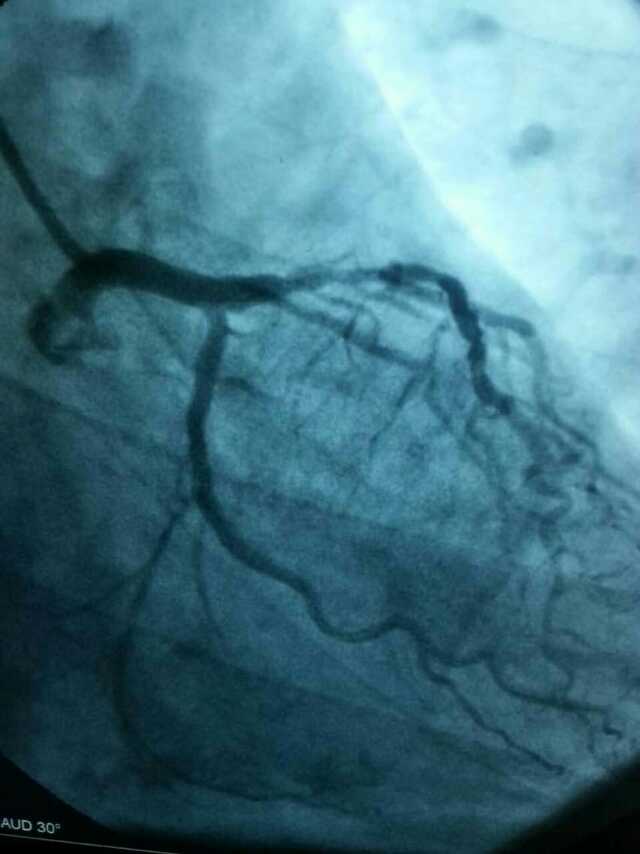

3月20日,家住翔安的庄先生为感谢伦理片 心血管内科的医护人员在第一时间对他的病情给予明确诊断,并及时采取有效治疗措施,让他的心脏病很快得到康复回家。特地送来一面写着“德医双馨,妙手回春”锦旗以表达他们满满的感激之情。